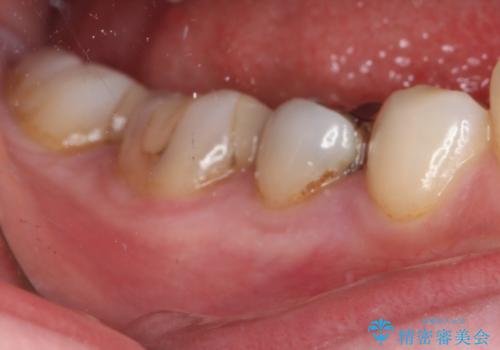

下の奥歯の虫歯をゴールドインレーで治療

- 奥歯の虫歯を心配して来院した患者様です。

レントゲン写真から、以前治療した詰め物の下に虫歯があることがわかりました。

精度が高く、虫歯の再発リスクの低いゴールドインレーで治療を行うこととしました。